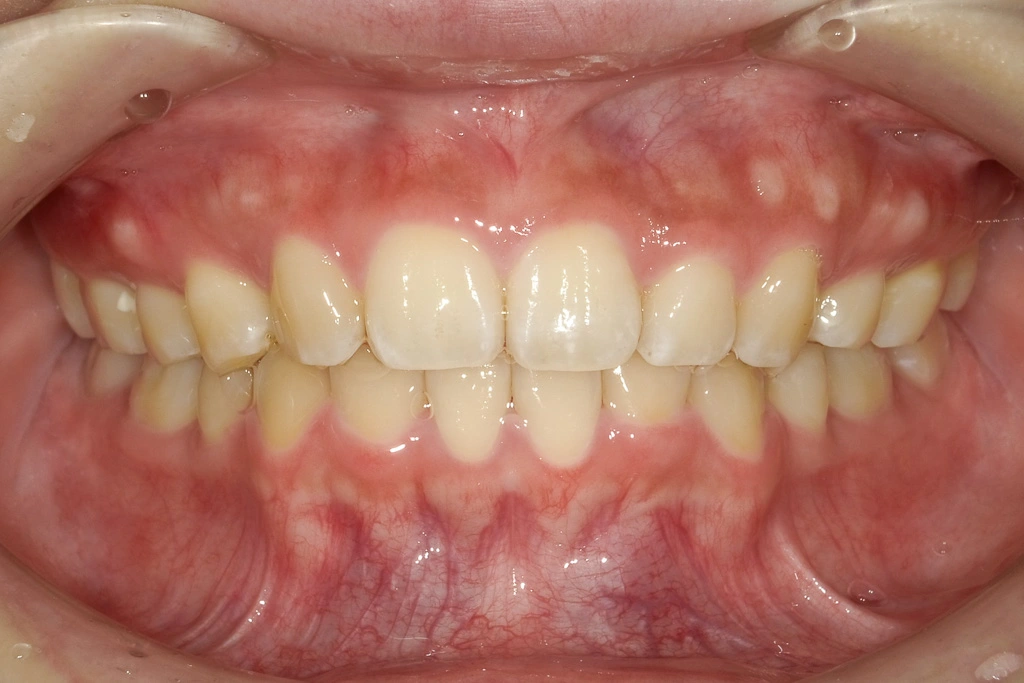

治療完了時

仕上がりを確認しています

最終チェックをしています。一緒に気になるところがないか確認しています。

治療内容:第1小臼歯を3本抜歯し、ワイヤータイプの装置で矯正しました。

治療費:ワイヤー矯正総額106万円〜178万円(税込)

治療期間:2Y